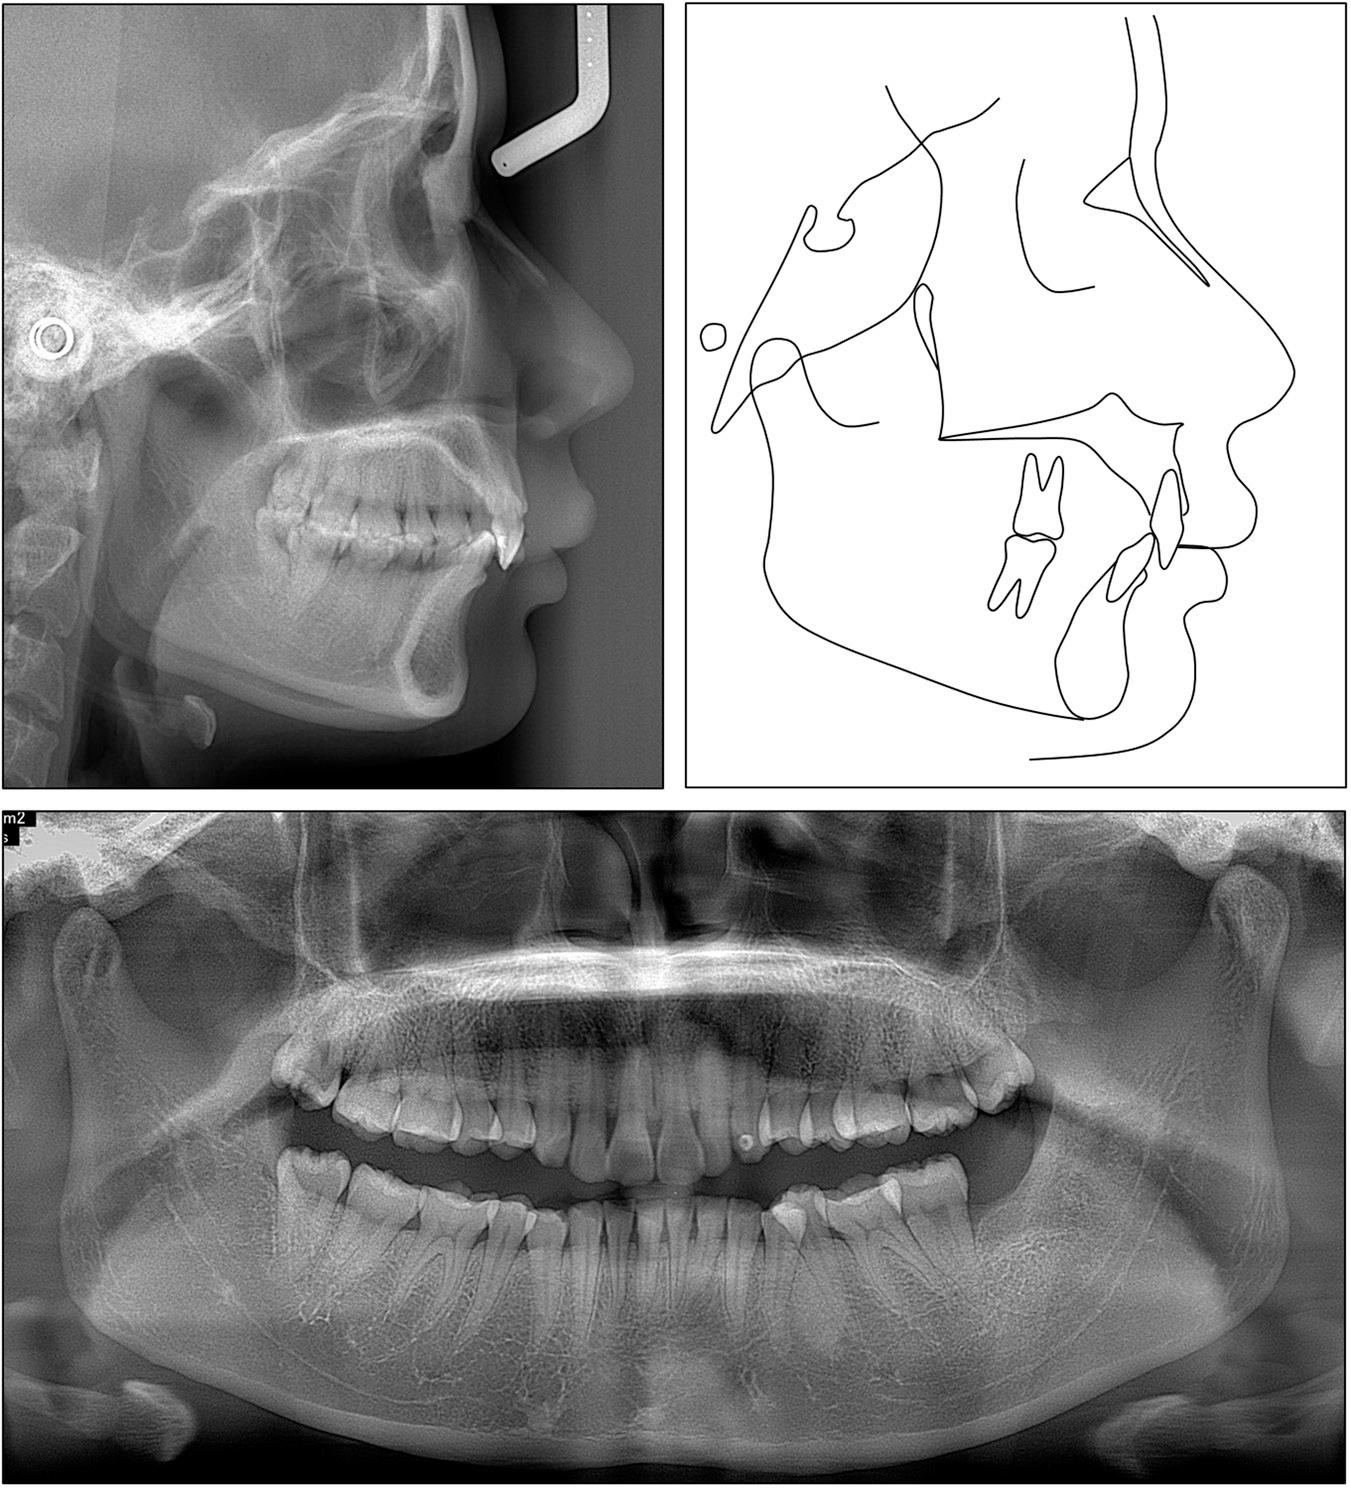

A cephalometric analysis showed that the skeletal Class II relationship was reduced (ANB: 8.0°) (Figure 14). The upper incisor torque significantly improved (U1/SN: 94.1°), while the lower incisors were proclined (IMPA: 106°). The panoramic radiograph confirmed acceptable root parallelism without root resorption. Cephalometric superimpositions showed the palatal root torque and intrusion of the upper incisors, the intrusion and proclination of the lower incisors, the distalisation of the upper molars, and the slight uprighting of the lower molars (Figure 15).

Case 2: post-treatment panoramic and cephalometric radiographs and tracing.